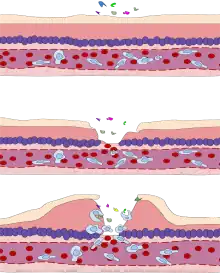

Vasodilation and increased permeability

As defined, acute inflammation is an immunovascular response to inflammatory stimuli, which can include infection or trauma.[20][21] This means acute inflammation can be broadly divided into a vascular phase that occurs first, followed by a cellular phase involving immune cells (more specifically myeloid granulocytes in the acute setting).[20] The vascular component of acute inflammation involves the movement of plasma fluid, containing important proteins such as fibrin and immunoglobulins (antibodies), into inflamed tissue.

Upon contact with PAMPs, tissue macrophages and mastocytes release vasoactive amines such as histamine and serotonin, as well as eicosanoids such as prostaglandin E2 and leukotriene B4 to remodel the local vasculature.[22] Macrophages and endothelial cells release nitric oxide.[23] These mediators vasodilate and permeabilize the blood vessels, which results in the net distribution of blood plasma from the vessel into the tissue space. The increased collection of fluid into the tissue causes it to swell (edema).[22] This exuded tissue fluid contains various antimicrobial mediators from the plasma such as complement, lysozyme, antibodies, which can immediately deal damage to microbes, and opsonise the microbes in preparation for the cellular phase. If the inflammatory stimulus is a lacerating wound, exuded platelets, coagulants, plasmin and kinins can clot the wounded area using vitamin K-dependent mechanisms[24] and provide haemostasis in the first instance. These clotting mediators also provide a structural staging framework at the inflammatory tissue site in the form of a fibrin lattice – as would construction scaffolding at a construction site – for the purpose of aiding phagocytic debridement and wound repair later on. Some of the exuded tissue fluid is also funneled by lymphatics to the regional lymph nodes, flushing bacteria along to start the recognition and attack phase of the adaptive immune system.

Acute inflammation is characterized by marked vascular changes, including vasodilation, increased permeability and increased blood flow, which are induced by the actions of various inflammatory mediators.[22] Vasodilation occurs first at the arteriole level, progressing to the capillary level, and brings about a net increase in the amount of blood present, causing the redness and heat of inflammation. Increased permeability of the vessels results in the movement of plasma into the tissues, with resultant stasis due to the increase in the concentration of the cells within blood – a condition characterized by enlarged vessels packed with cells. Stasis allows leukocytes to marginate (move) along the endothelium, a process critical to their recruitment into the tissues. Normal flowing blood prevents this, as the shearing force along the periphery of the vessels moves cells in the blood into the middle of the vessel.

Cellular component

Leukocyte extravasation

Various leukocytes, particularly neutrophils, are critically involved in the initiation and maintenance of inflammation. These cells must be able to move to the site of injury from their usual location in the blood, therefore mechanisms exist to recruit and direct leukocytes to the appropriate place. The process of leukocyte movement from the blood to the tissues through the blood vessels is known as extravasation and can be broadly divided up into a number of steps:

- Leukocyte margination and endothelial adhesion: The white blood cells within the vessels which are generally centrally located move peripherally towards the walls of the vessels.[25] Activated macrophages in the tissue release cytokines such as IL-1 and TNFα, which in turn leads to production of chemokines that bind to proteoglycans forming gradient in the inflamed tissue and along the endothelial wall.[22] Inflammatory cytokines induce the immediate expression of P-selectin on endothelial cell surfaces and P-selectin binds weakly to carbohydrate ligands on the surface of leukocytes and causes them to "roll" along the endothelial surface as bonds are made and broken. Cytokines released from injured cells induce the expression of E-selectin on endothelial cells, which functions similarly to P-selectin. Cytokines also induce the expression of integrin ligands such as ICAM-1 and VCAM-1 on endothelial cells, which mediate the adhesion and further slow leukocytes down. These weakly bound leukocytes are free to detach if not activated by chemokines produced in injured tissue after signal transduction via respective G protein-coupled receptors that activates integrins on the leukocyte surface for firm adhesion. Such activation increases the affinity of bound integrin receptors for ICAM-1 and VCAM-1 on the endothelial cell surface, firmly binding the leukocytes to the endothelium.

- Migration across the endothelium, known as transmigration, via the process of diapedesis: Chemokine gradients stimulate the adhered leukocytes to move between adjacent endothelial cells. The endothelial cells retract and the leukocytes pass through the basement membrane into the surrounding tissue using adhesion molecules such as ICAM-1.[25]

- Movement of leukocytes within the tissue via chemotaxis: Leukocytes reaching the tissue interstitium bind to extracellular matrix proteins via expressed integrins and CD44 to prevent them from leaving the site. A variety of molecules behave as chemoattractants, for example, C3a or C5, and cause the leukocytes to move along a chemotactic gradient towards the source of inflammation.